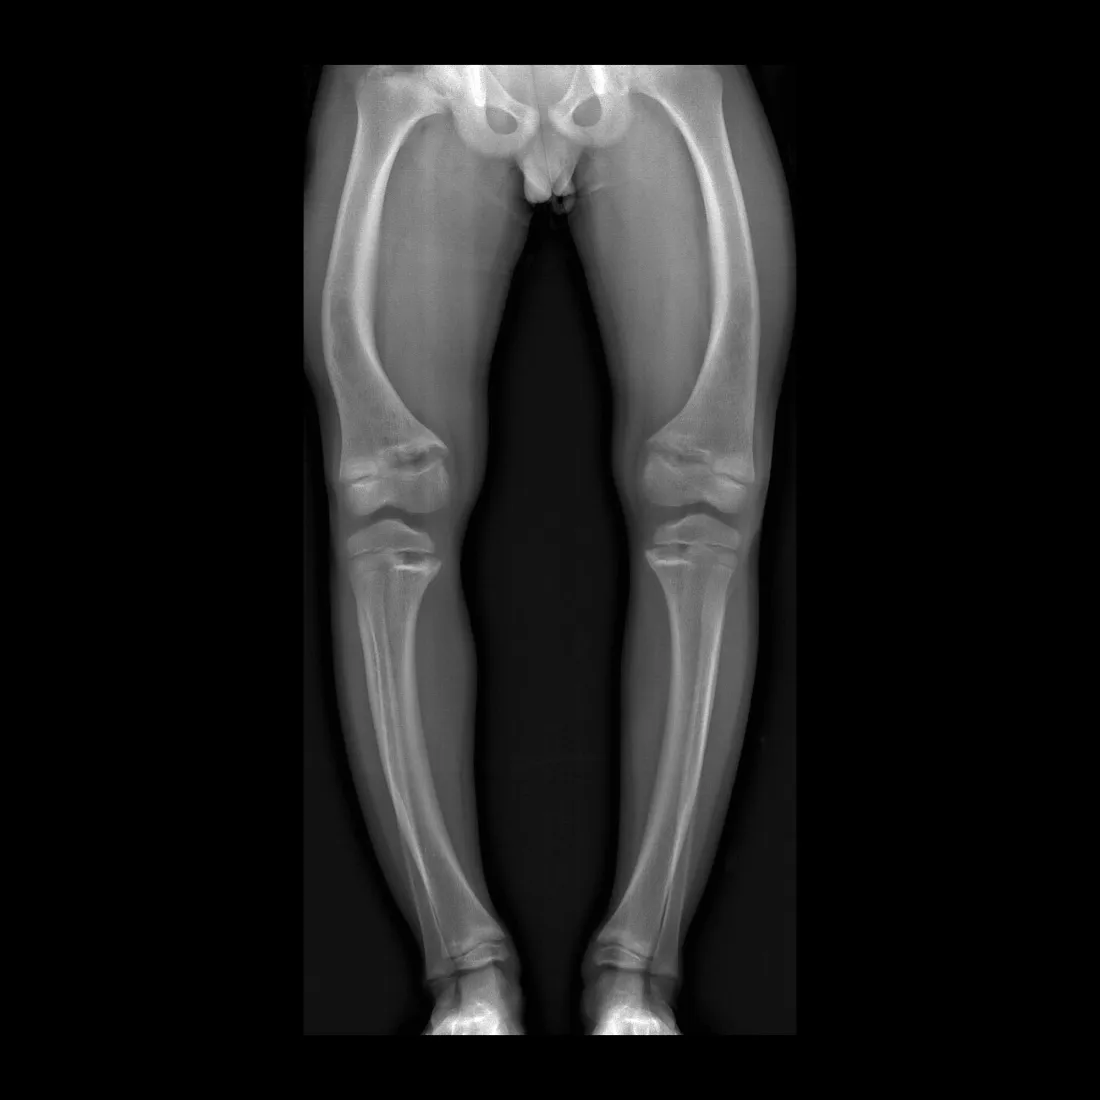

What is the most common symptom of rickets?

Bowed legs.

What is the best imaging modality to diagnose rickets?

Plain X-rays.

What is seen on X-rays of a rickets patient?

Bowed legs and widened wrists due to metaphyseal cupping.